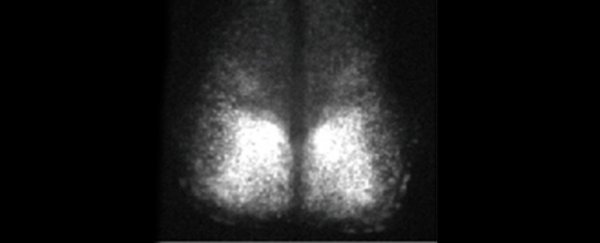

The team tested the device using tissue from the mouse suprachiasmatic nucleus, a complex part of the brain that governs circadian rhythms.

The mice themselves were knock-in mice in which circadian rhythm activity in the brain was linked to the production of a highly fluorescent protein.

By measuring the level of bioluminescence coming from the brain tissue, they were able to see that tissue kept alive by their system stayed active and functional for over 25 days with nice circadian activity.